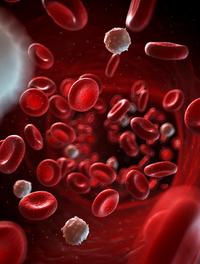

L’EFS est un acteur vital pour le système de santé français, aussi vital, pourrait-on dire, que le sang l’est pour l’organisme. Acteur public, placé sous la tutelle du Ministère de la santé et de la prévention, il est garant de l’autosuffisance du pays en produits sanguins labiles. Mais pas seulement ! Avec 10 000 professionnels répartis dans toute la métropole et les t